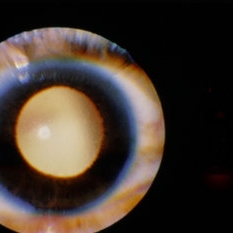

Myelinated Nerve Fiber Layer Causing Leukocoria

Jan 30 2015 by H. Michael Lambert, MD

Leukocoria due to extensive myelination of optic nerve head.

Condition/keywords: leukocoria, myelinated nerve fiber layer